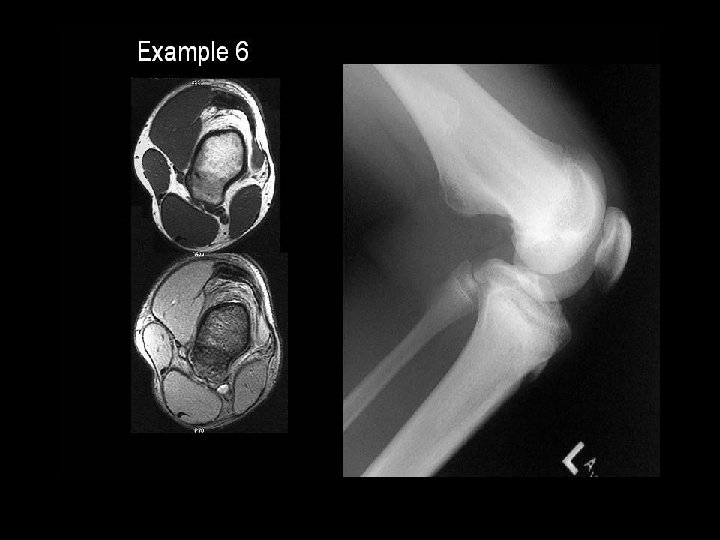

A 14 year old boy presents with pain and a mass above the knee. Take a look at the AP and lateral radiographs first.